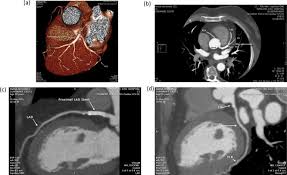

Evaluation Of Soft Plaque Stenoses In Coronary Artery Stents Using Conventional And Monoenergetic Images First In Vitro Experience And Comparison Of Two Different Dual Energy Techniques Hickethier Quantitative Imaging In Medicine And Surgery

Evaluation Of Soft Plaque Stenoses In Coronary Artery Stents Using Conventional And Monoenergetic Images First In Vitro Experience And Comparison Of Two Different Dual Energy Techniques Hickethier Quantitative Imaging In Medicine And Surgery from cdn.amegroups.cn